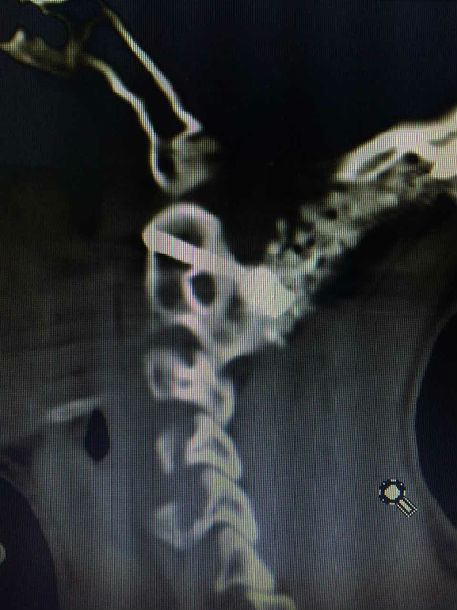

手术前CT显示:寰枢椎脱位

手术后复查CT显示:寰枢椎脱位完全复位,脊髓受压明显改善,枕颈固定位置良好,局部植骨融合。